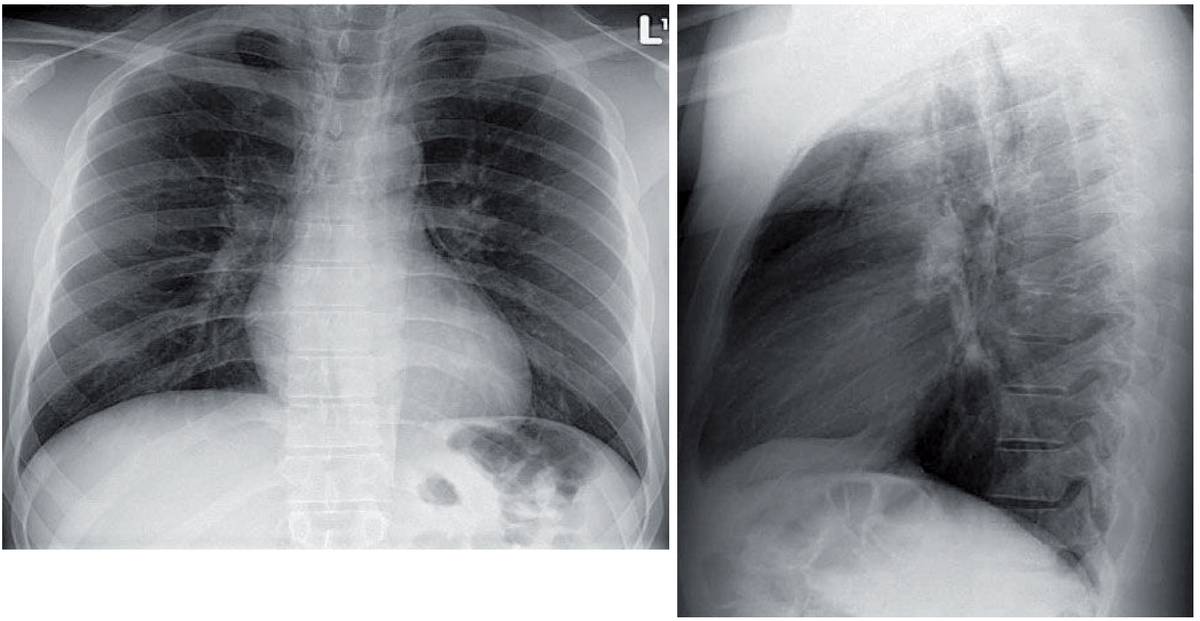

Chest x-ray of a 22-year-old man with severe sudden onset of chest pain

22-year-old man with severe sudden onset of chest pain

22-year-old man complains of severe sudden onset of chest pain.

What’s the diagnosis ?